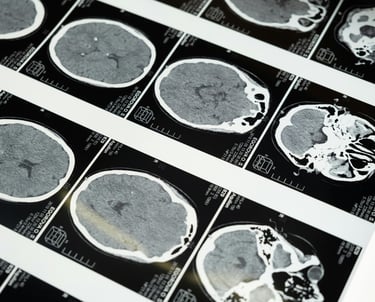

O SegmentaR foca na segmentação automática das três regiões fundamentais para o planejamento de radioterapia: cabeça e pescoço, tórax e pelve. Essas são as regiões essenciais que todo profissional precisa para uma segmentação precisa e eficiente.

Cabeça e Pescoço

Mandíbula

Cérebro

Tronco Cerebral

Cavidade Oral

Cóclea Esquerda

Cóclea Direita

Esôfago

Olho Direito

Olho Esquerdo

Glândula Tireoide

Laringe

Cristalino Direito

Cristalino Esquerdo

Quiasma Óptico

Nervo Óptico Esquerdo

Nervo Óptico Direito

Parótida Esquerda

Parótida Direita

Medula Espinhal